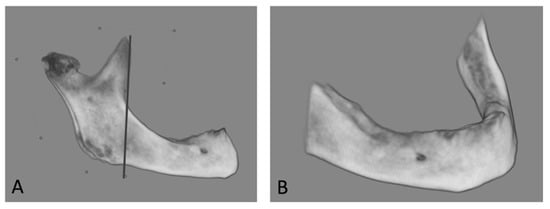

2.5. CBCT Measurements